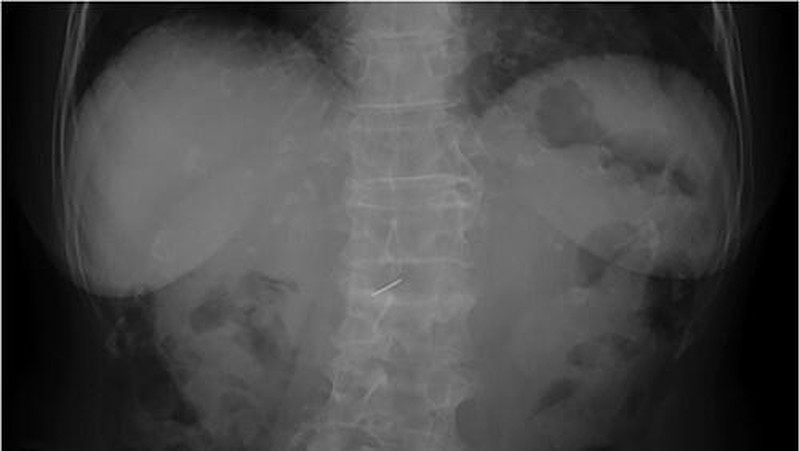

Hasil rontgen abdomen seorang nenek 81 tahun di Jepang memperlihatkan bayangan putih menyerupai jarum pada area dekat tulang belakang lumbal kedua. Temuan ini muncul saat pemeriksaan pencernaan rutin. (Foto: Journal of Surgical Case Reports)